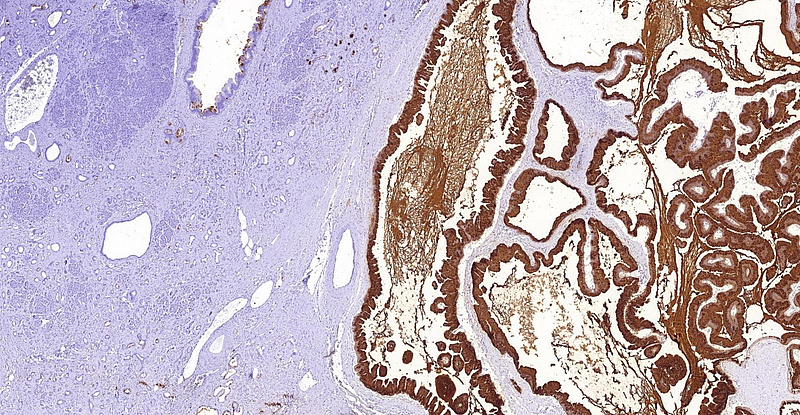

Immunohistochemistry demonstrated diffuse positivity for MUC5AC (Panel D). MUC6 was focally positive within the oncocytic component of the tumour (Panel E). Of note, intra- and interlobular fibrosis with remarkable atrophy of the acini was detected in the non-neoplastic area of the pancreas, mimicking well-differentiated (tubular) invasive carcinoma (Panel F). Endocrine cells were comparatively spared and the lobocentric architecture was preserved.